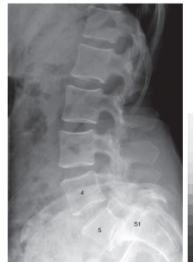

-Refer to the figure. Name the view.

A) Anteroposterior view of the lumbar spine

B) Anteroposterior view of the lumbosacral spine

C) Oblique view of the lumbosacral spine

D) Lateral view of the lumbosacral spine